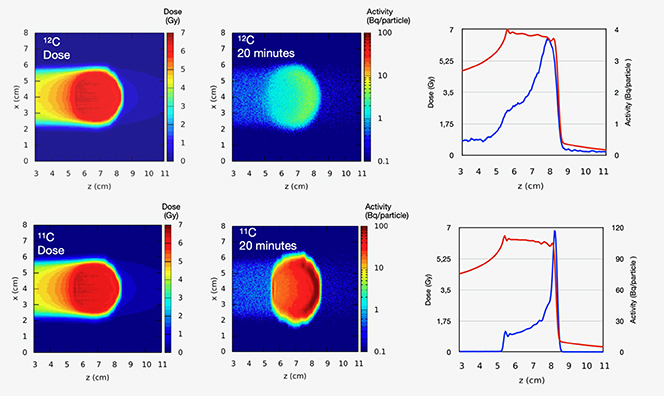

Proton and ion beam therapy has growing potential in dealing with difficult-to-treat tumours, for example, because of the risk of damaging neighbouring sensitive tissues such as the brainstem or visual nerves in the case of head tumour treatments. Also, some treatments may benefit from the use of particles that deliver doses with greater radiobiological effectiveness (RBE) and higher local precision, notably carbon, and in the near future also helium ions.

Recent investigations using ultra-short and ultra-high dose rates (called FLASH) of electron beams showed growth retardation of tumours with the same effect as in conventional therapy, but with minimized impact to the surrounding tissue. FLASH with proton and ion beams is expected to offer additional healthy tissue sparing from beam stopping in the tumour—but the research on this topic is still not completed, and the experiments and evaluations are ongoing. Healthy tissue sparing with FLASH would enable a dose increase as well as a significant reduction of treatment time without additional aggravations. These new key findings may influence the accelerator development for particle therapy considerably in the next future.

For protons and 3He/4He similar radio-biological properties have been determined, but the lateral scattering is reduced by nearly 50% in the case of helium ions versus protons (figure 5.7). In recent years, helium ions again became of interest for clinical cases where neither protons nor carbon ions are ideally suited, especially for treating paediatric tumours. Currently, patient irradiations with scanned 4He ions at the Heidelberg Ion beam Therapy Center (HIT) in Germany are used only in 'treatment attempts' ('individuelle Heilversuche') and will go into regular operation by mid 2024. Other ion therapy facilities in Europe (e.g., CNAO in Italy and MedAustron in Austria) have also started technical upgrades to produce helium ion beams in the near future.

Standard image High-resolution imageRecent studies have shown that 3He ions can be a viable alternative to 4He, as they can produce comparable dose profiles, demanding slightly higher kinetic energy per nucleon, but less total kinetic energy. This results in 20% less magnetic rigidity needed for the same penetration depth which may be of importance for the design of future compact therapy accelerators like superconducting synchrotrons or energy-variable cyclotrons.